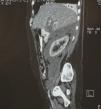

La tomografía axial computada reveló marcada dilatación de la vía biliar intra- y extrahepática, sin lograr identificar la vesícula biliar; además, se observó la presencia de líquido en el área pararrenal anterior y posterior (figs. 1–3).